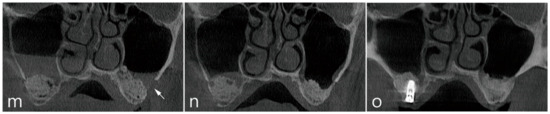

Maxillary sinus augmentation was performed on a 65-year-old male non-smoker with no reported systemic diseases. Panoramic radiographs revealed missing posterior maxillary molars. Subsequently, the left and right maxillary sinuses were pneumatized with resorption of the residual bone. CBCT revealed alveolar crestal height to be approximately 3 mm (Figure 2a) with a healthy Schneiderian non-compromised membrane, no thickening of the membrane was noted (Figure 2b). The lateral bone was noted to be thin without the presence of the posterior superior alveolar artery (Figure 2c,d). In the right maxillary sinus, sinus floor elevation via the lateral window approach was performed without the perforation of the sinus membrane, wherein, the lateral bone lid was removed (Figure 2e). The elevated sinus was filled with Osteon III (Genoss, Suwon, Korea) (Figure 2f), and the removed lateral bone lid was repositioned (Figure 2g). Flaps were closed (Figure 2h). In the left maxillary sinus, the lateral bone lid was removed, and subsequently, a large perforation of the Schneiderian membrane was observed (Figure 2i). In accordance with the proposed approach of the open lateral window technique (Figure 2j), the upper part of the lateral window site was left open after bone grafting (Figure 2k). The flap was closed at the lateral window site without membrane coverage (Figure 2l). Postoperatively, nasal bleeding and facial swelling were observed with eventual complete recovery, where no sinonasal complications occurred in the left and right maxillary sinuses. The patient underwent implant installation only in the right maxillary sinus 6 months after the maxillary sinus bone graft. A CBCT of the left maxillary sinus was acquired a year later (Figure 2m). Imaging revealed no membrane thickening and the exposed bone graft substitute was not covered with soft tissue (Figure 2n). No differences in membrane thickening of the left and right maxillary sinuses was observed. The volume of the implanted sinus bone graft had subsequently not changed, and the opened lateral window site was also filled with bone (Figure 2o).

Figure 2.

Case 2. Radiological findings of case 2. (a) On the panoramic radiograph before the procedure, pneumatization of the left and right maxillary sinuses and insufficient residual alveolar bone was observed; (b) Membrane thickening was not observed in the left and right maxillary sinuses on the panoramic image of the preoperative CBCT; (c) In the coronal image of the preoperative CBCT, the Schneiderian membrane was very thin and the buccal bone was not thick; (d) In the axial image of the preoperative CBCT scan, sinus membrane thickening was not found. Clinical picture of the lateral window approach with unintentional split-mouth design. (e) A lateral window approach performed in the right maxillary sinus without perforation of the Schneiderian membrane. After removal of the lateral bone window, the sinus membrane was separated from the sinus floor and elevated; (f) The MSA was performed. (g) The lateral bone window was repositioned; (h) The flap was closed; (i) An open lateral window approach performed on the left maxillary sinus with wide perforation of the Schneiderian membrane. The Schneiderian membrane was widely perforated during sinus floor elevation; (j) The Prichard elevator was placed in the maxillary sinus, and bone grafting was performed on the sinus floor; (k) After withdrawing the Prichard elevator, the upper part of the lateral window was opened. Membrane covering or repositioning was not performed; (l) The flap was closed. (m) Coronal image of CBCT immediately after the procedure. An open lateral window of the left maxillary sinus was observed; (n) Coronal image of CBCT 2 weeks after the procedure. The open lateral window was observed to close again. No leakage of the bone graft substitute was observed and there was no thickening of the Schneiderian membrane; (o) Coronal image of CBCT 1 year after surgery. An implant was placed in the right maxillary sinus, and an implant is scheduled to be installed in the left maxillary sinus. Membrane thickening was not observed. There was no additional leakage of bone graft.